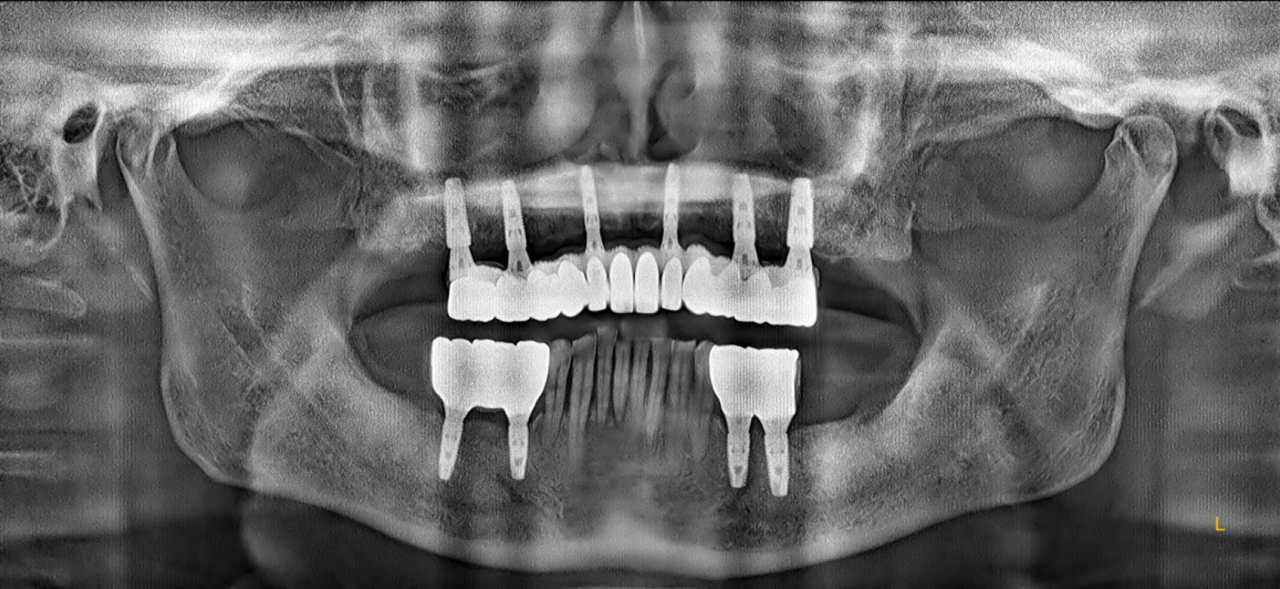

永久修复3年随访:

上下颌边缘骨稳定,零骨吸收

通过修复后口内照观察到,美学效果良好,无基台种植体配合性能相关的周围炎。通过医学影像观察到,修复三年后种植体周围无骨吸收,患者非常满意。